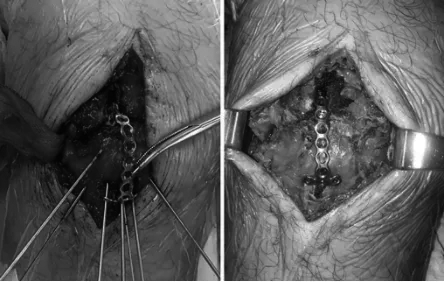

图3. HPS“T”形接骨板复位髌骨骨折术中照片;(A)复位后置入预塑形钢板,克氏针临时固定;(B)钢板、螺钉固定完成情况。

扎骨针怎么装髌骨下极粉碎骨折怎么办?7种固定技术详解与术式选择_https://www.jmylbn.com_新闻资讯_第19张